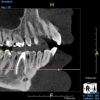

(4.) In a CBCT image axial view, the MB1 and MB2 canals are readily visible in tooth No. 14, and in the coronal view, these two separate canals can be seen to merge into a single apical opening.

Figure 4

Being able to see the number and shape of the canals accurately prior to treatment is the desire of any clinician who performs endodontics. Research suggests that, due to improved diagnostic accuracy, the final treatment plan may change in up to 50% of endodontic cases if CBCT is used rather than traditional 2D imaging.14,15 The question of whether or not a patient has an MB2 canal can be answered prior to opening the access preparation (Figure 4 and Figure 5). Visualizing single canals that bifurcate in the apical or middle third of the root or those that merge to a single apical opening can help clinicians to understand their instrumentation needs in advance. In addition, the ability to measure the length and shape of a canal planned for instrumentation prior to utilizing an apex locator helps to confirm any measurements obtained by other means. It should also be noted that the ability to see a pathosis in 3 dimensions and to involve the patient in understanding his or her condition prior to any decision-making allows for definitive treatment planning. In fact, many patients have pathoses associated with teeth that are asymptomatic that remain unknown to them until they are visually presented with the evidence (Figure 6).